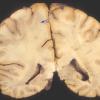

MYELIN (IMMUNE-MEDIATED)

AHL